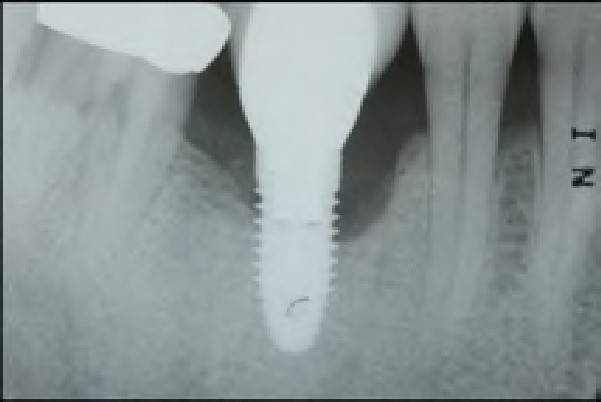

Fig 5. View of a radiograph taken of an implant in September 2009.

Figure 5

Fig 6. To demonstrate how rapidly peri-implantitis bone loss occurs, a radiograph of the same implant shown in Fig 5 taken 3 years later (left) shows significant bone loss, and the photograph (right) shows soft-tissue loss.

Figure 6